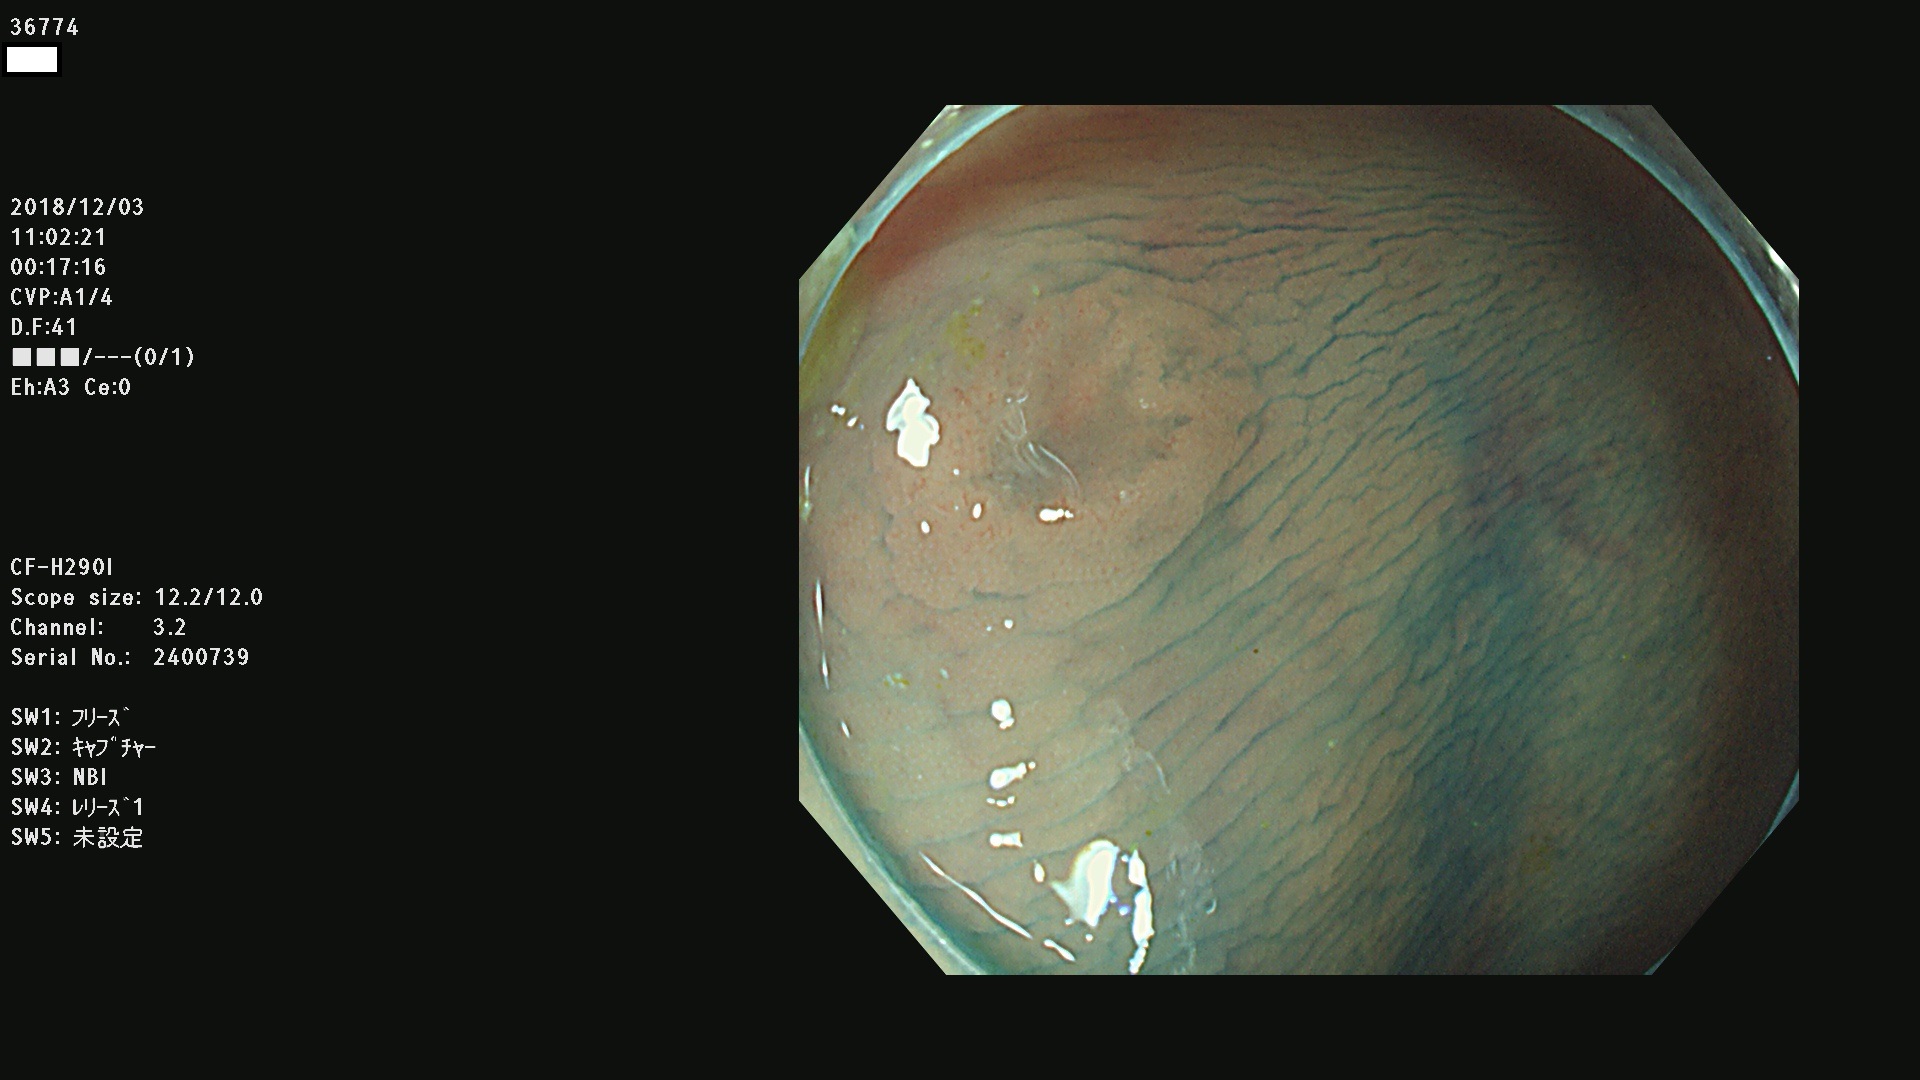

36700 36701 36702 36704 36705 36707 36708 36710 36712(SSAPのみ) 36714 36715 36716 36717 36718 36721 36723 36724 36730 36731 36732 36734 36735 36736 36738 36739 36742 36744 36745 36746 36749 36752(SSAPのみ) 36754 36756 36758 36759 36760 36731 36732 36734 36737 36738 36739 36771(SSAPのみ) 36772 36773 36774 36775 36776 36777 36780 36781 36783 36785 36786 36788 36790 36792 36794 36797 36798

発見困難で危険性の高い平坦型病変(上記100名より抽出)